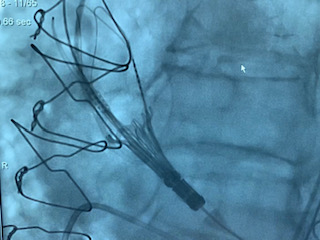

Liberación de una TAVI

Liberación TAV

Liberación TAVI